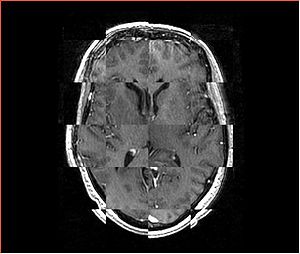

• Checkerboard appearance of unregistered images for the representative data of interest

• Case10